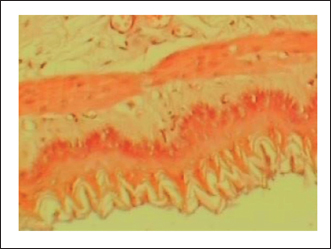

The gastric tissue slides were examined under a microscope for morphological changes such as hyperemia, hemorrhage, edema, necrosis, inflammatory changes, distortion, erosion, and ulcers caused by the destructive effects of indomethacin on stomach tissues. No pathological changes were observed in the normal control group (Fig. 1). Rats in the ulcer control group showed significant damage to the surface epithelium, necrotic areas penetrating the mucosal layer, and severe edema of the submucosal layer. Additionally, there was congestion with infiltration of inflammatory cells (Fig. 2). Histological results revealed that the treated rats with ranitidine had less protection of the gastric lining due to mild infiltration of leucocyte and edema in the submucosal layer, in addition to less disruption in both the superficial and deep mucosal layers. Treatment doses (300, 400 and 500 mg/kg) with P. farcta extract. Groups treated with P. farcta extract (300 and 400 mg/ kg) showed mild infiltration of inflammatory cells, edema, or significant disruption of the deep mucosa (Figs 5 and 6) while, P. farcta extract group (500mg/ kg) prevented histological changes and showed no infiltration of inflammatory cells, edema, or significant disruption of the deep mucosa (Figs 3, 4 and 7).

Fig. 2. Normal control group received distilled water, No pathological changes were observed.

Fig. 7. Prosopis farcta extract (500 mg/kg) prevented histological changes, nofiltration of inflammatory cells, edema, or distruption of deepmucosa.